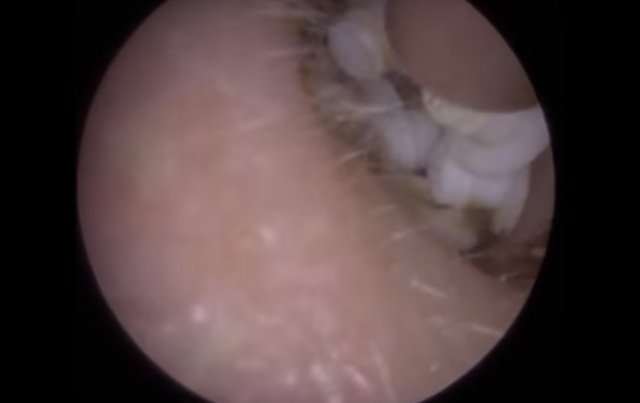

30 yıl boyunca geçmeyen bir baş ağrısı ile yaşayan bir kişi gittiği doktoru şoke etti. Yıllarca baş ağrısı çeken 59 yaşındaki adamın yaşadıkları kan dondurdu. Adamın kafasından öyle bir şey çıktı ki, doktorlar bile şaştı kaldı. İşte şoke eden olayın detayları...